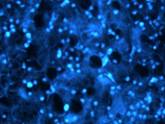

UV fluorescence microscopic image of the cryosections of B16 melanoma margins after uptake of AuSPION, with well defined border and high fluorescence in epidermis and intracellular in plasma lemma, but not in cell nucleus (x 60).

UV fluorescence image of B16 melanoma cells after uptake of gold coated maghemite superparamagnetic nanoparticles, which revealed cellular uptake of gold nanoparticles (x 60) |

UV fluorescence microscopic image of the cryosections of B16 melanoma injected with AuSPION in UV spectrum. The image has shifted from green (see previous image) to blue due to the uptake of gold nanoparticles (x 60)

The edges of melanoma are much sharper in UV fluorescence than in visible fluorescence |